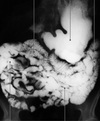

34

Name the structure and the contrast used

Stomach, barium contrast (X-ray)

35

Stomach is found in the…

Epigastrium/Left hypocondrium